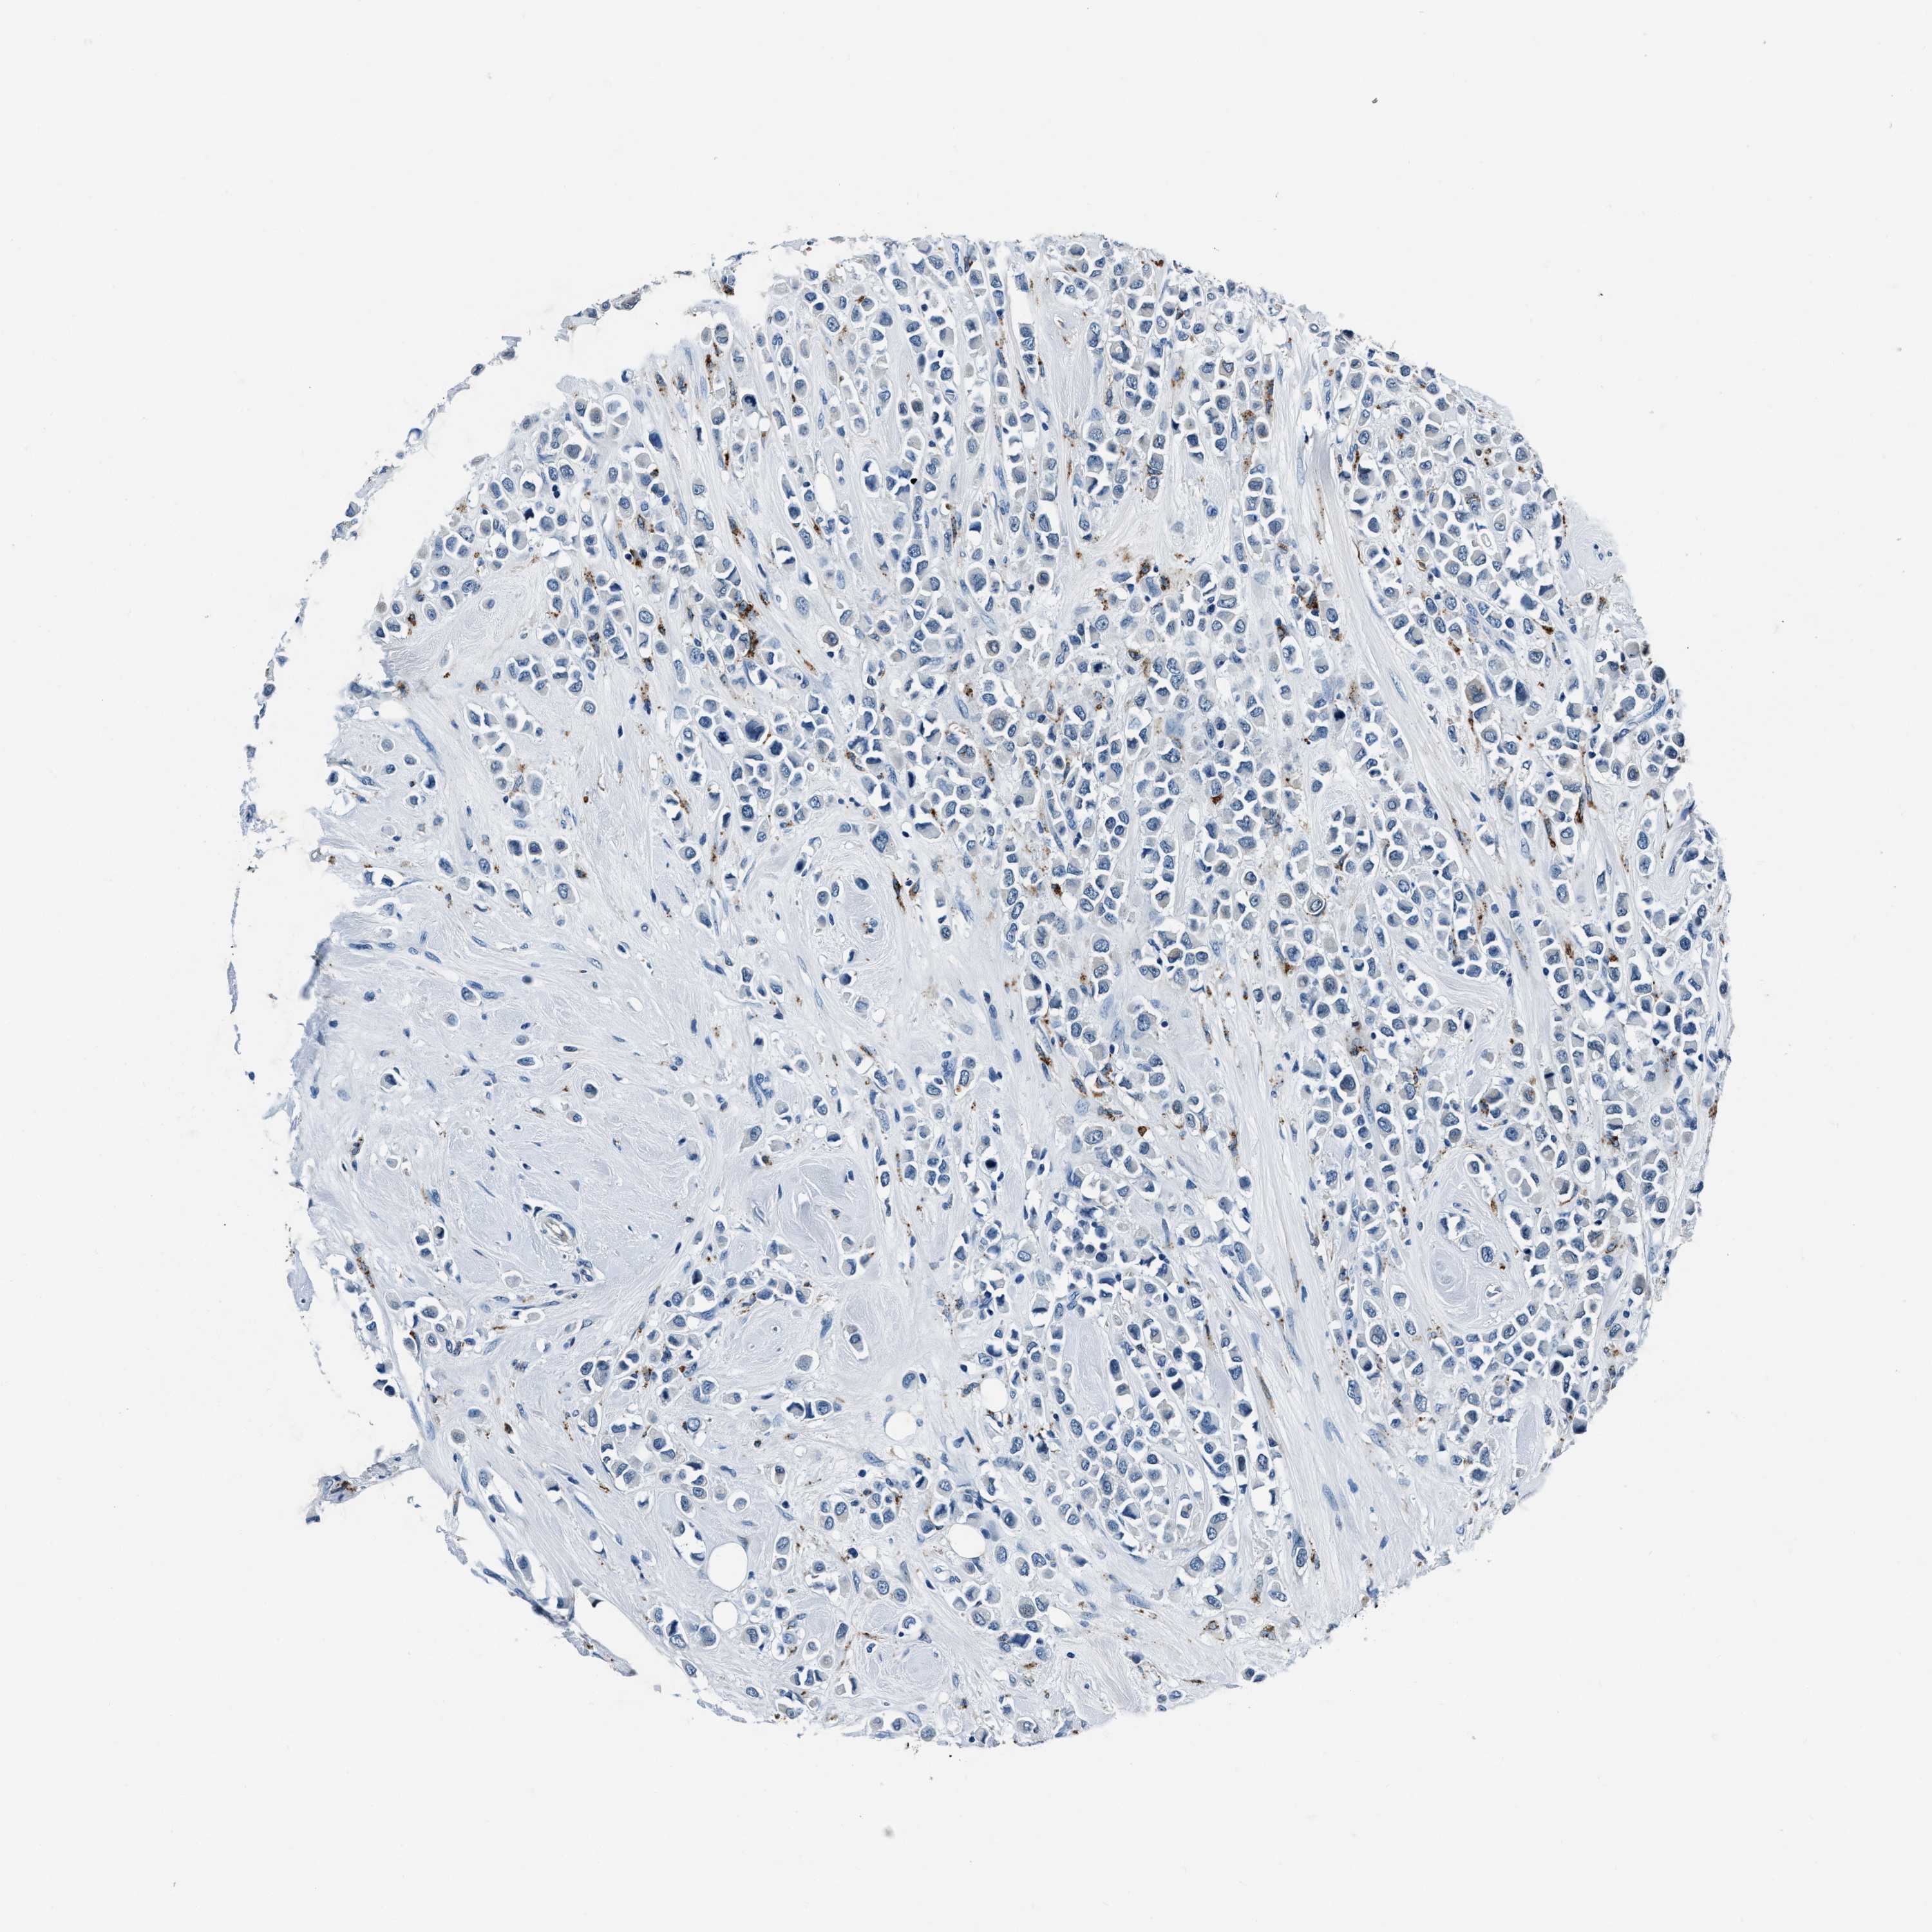

BRCA TCGA BRCA VALIDATION PROTEIN EXPRESSION